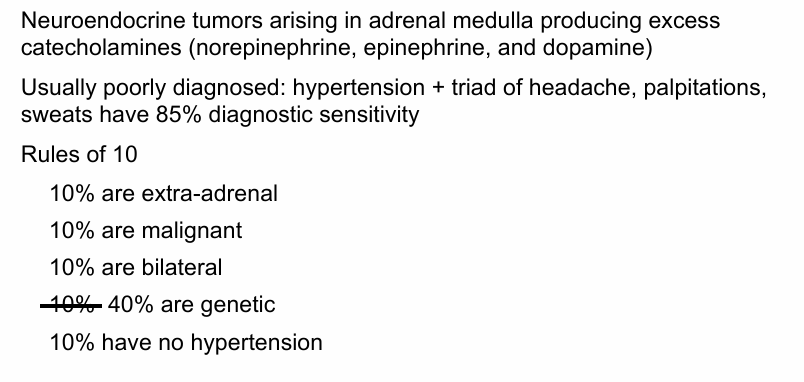

germline mutations associated with pheochromocytoma and paraganglioma